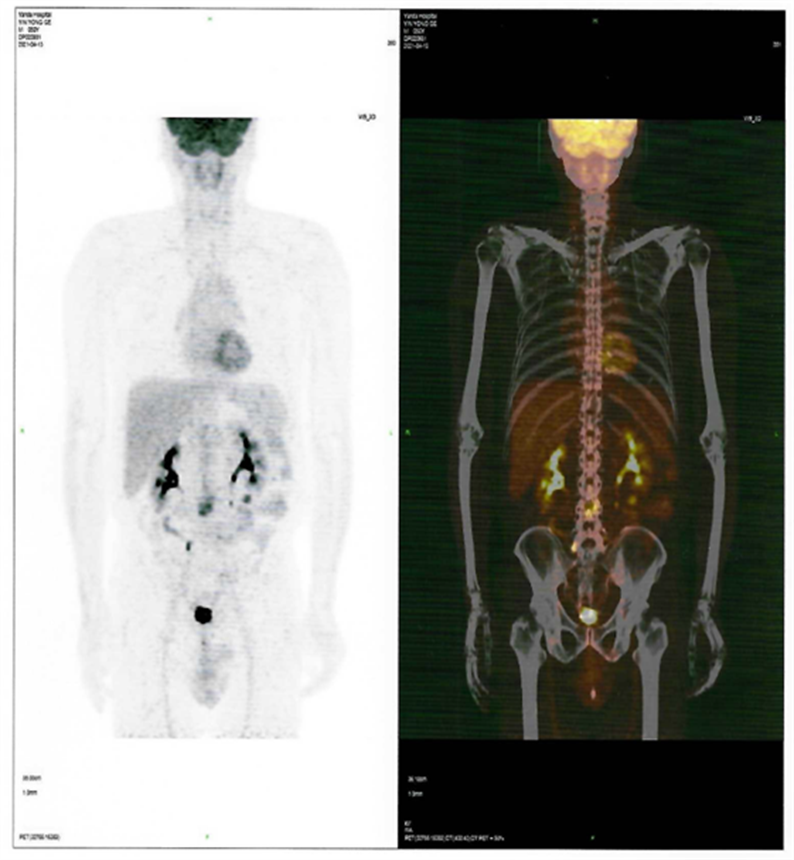

近日,燕達陸道培醫(yī)院血液科二病區(qū)傳來好消息,一位罹患T細胞淋巴瘤前期在美國治療復(fù)發(fā)的患者,428日,在我院回輸CD7 CAR-T細胞,526日經(jīng)PET-CT檢查,顯示CR(完全緩解)。

患者CAR-T 前后PET-CT檢查結(jié)果對比圖

CAR-T治療前

2021412日,患者來到燕達陸道培醫(yī)院,希望借助我院的CD7 CAR –T臨床試驗項目獲得一線生機?;颊叱跞朐簳rPET-CT檢查提示:腫瘤細胞累及多處腸系膜和腹部肌肉軟組織;骨髓未累及。